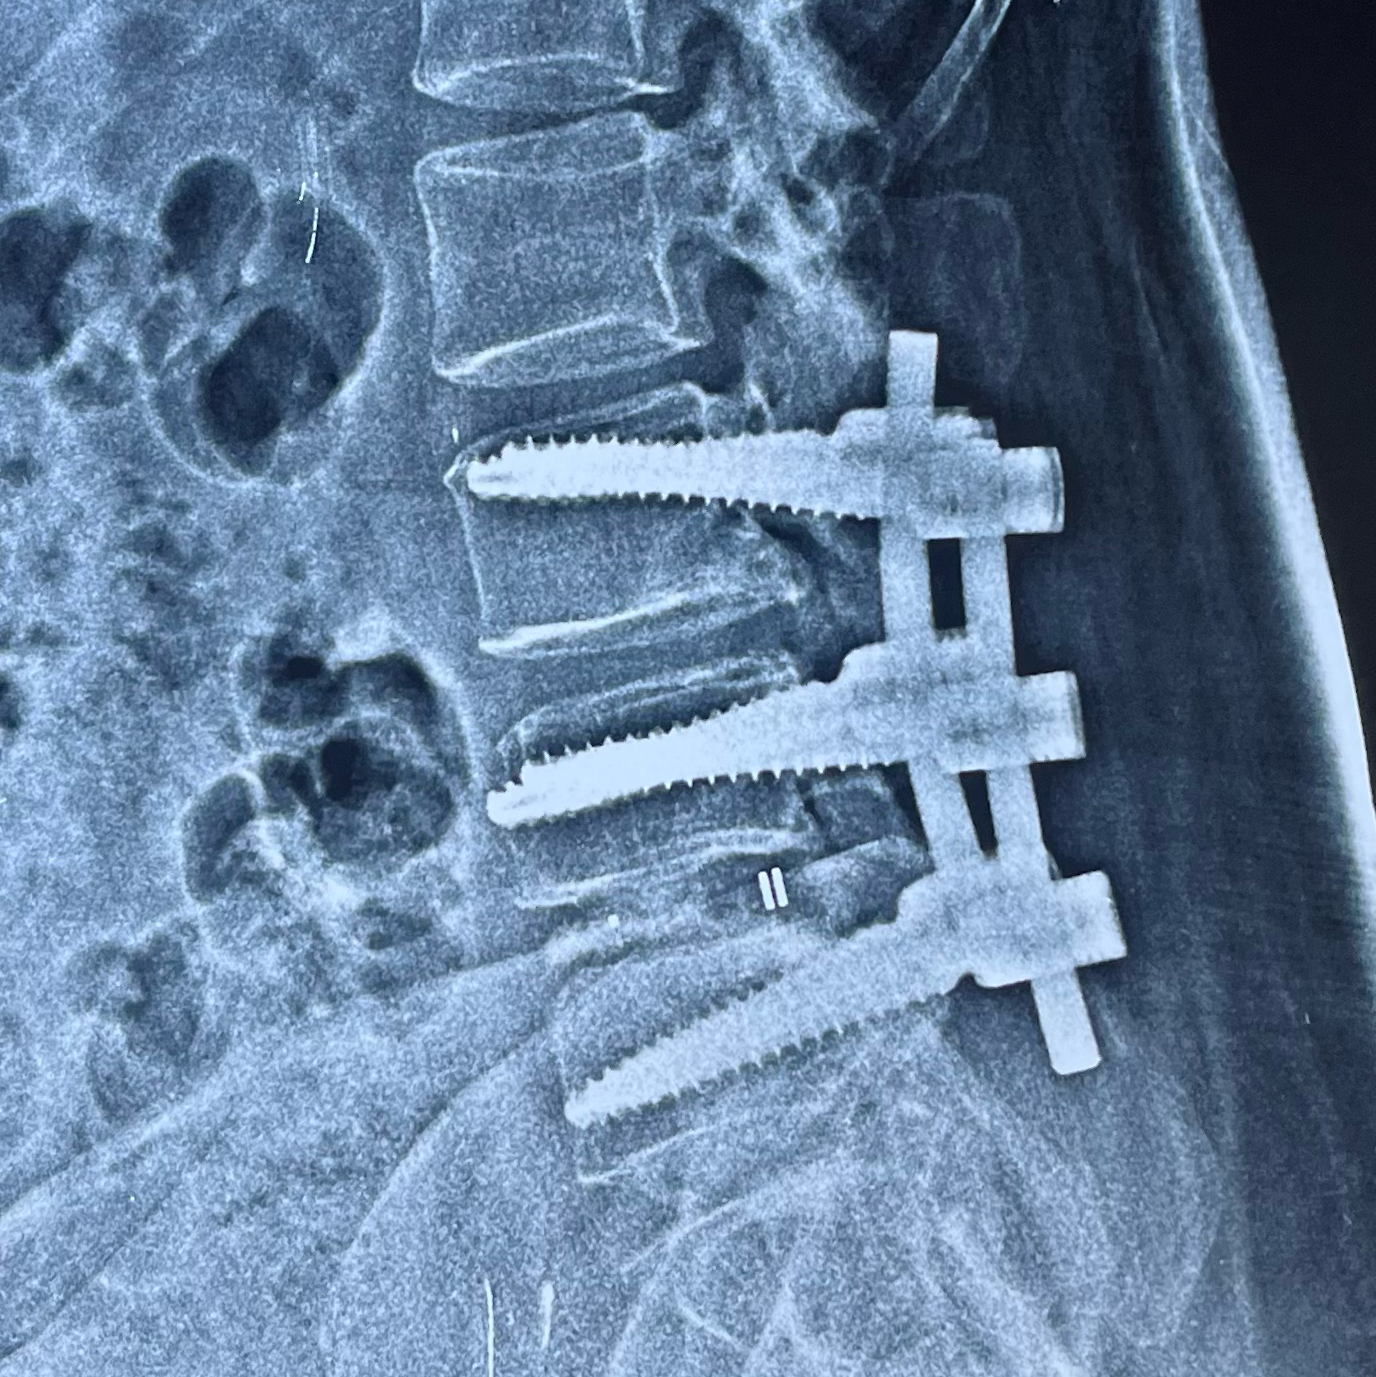

TLIF Spinal fusion for Spondylolisthesis L45